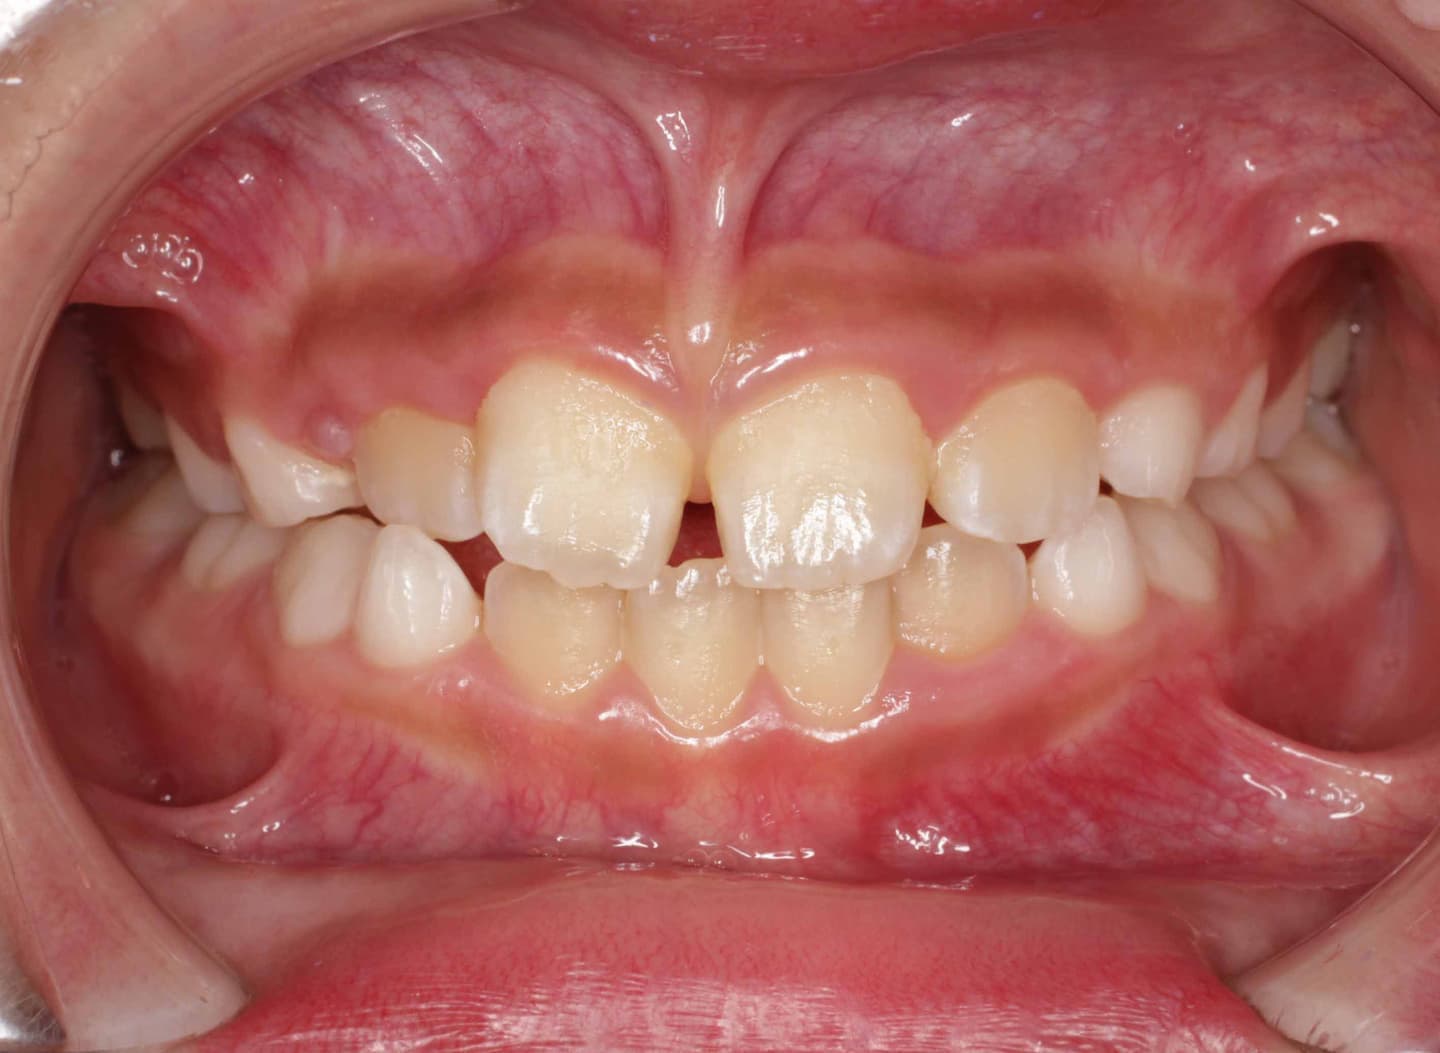

治療後(12ヶ月後)